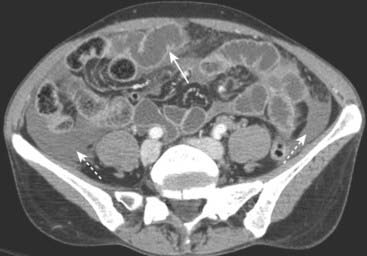

image

Figure 17-12 Bladder ruptures, extraperitoneal and intraperitoneal.

A, Contrast-containing urine (solid white arrows) has leaked into the extraperitoneal spaces after being instilled into a perforated bladder following pelvic fractures. Contrast, the tip of a Foley catheter, and air are seen inside of the partially filled urinary bladder (B). B, Intraperitoneal bladder ruptures are less common and may occur with blunt trauma. The contrast flows freely away from the bladder (B) up the paracolic gutters (solid white arrows) and outlines loops of bowel (dotted white arrow).